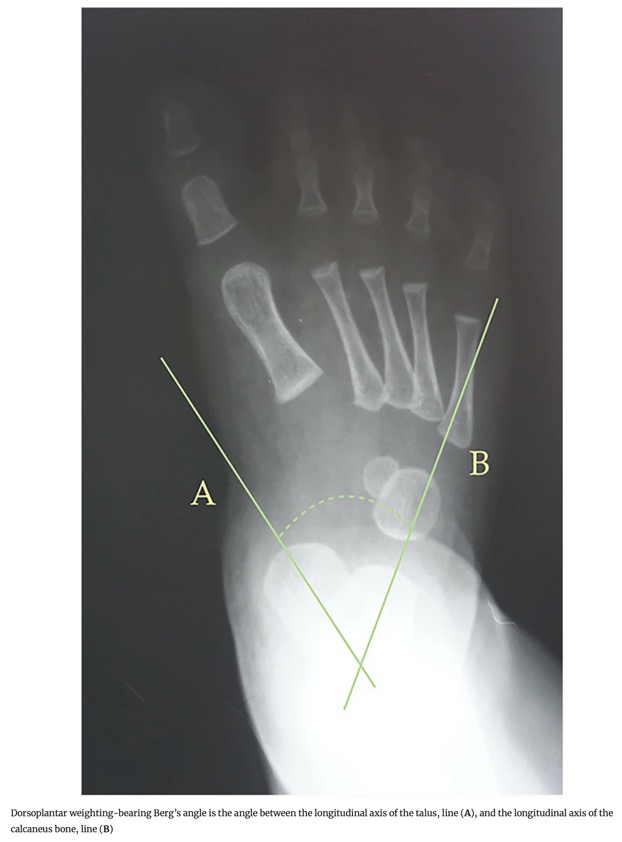

- 4. Angle de Berg : Angle entre l'axe longitudinal du talus et l'axe longitudinal du calcanéus.